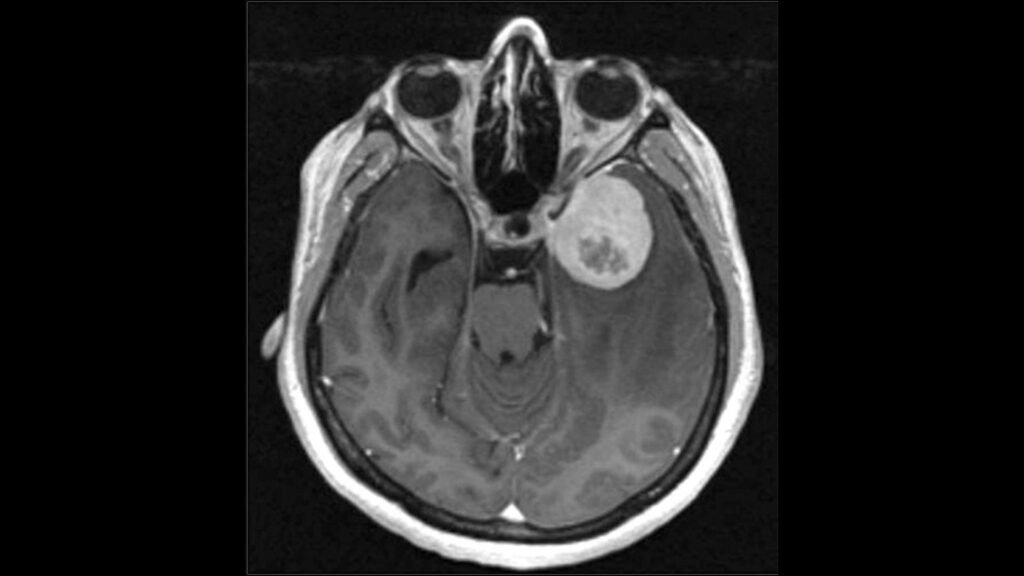

Rochester, Minggu 23 November 2025–VNNMedia- Sebuah studi multi-institusi yang dipimpin oleh Mayo Clinic menunjukkan temuan signifikan yang dapat mengubah cara dokter mendiagnosis dan menangani meningioma, jenis tumor otak yang paling umum

Meningioma umumnya dianggap jinak dan diklasifikasikan dalam tiga tingkatan berdasarkan pertumbuhan. Namun, penelitian yang menganalisis lebih dari 1.200 meningioma dari tiga negara ini menemukan bahwa tumor positif TERT-meskipun secara resmi berlevel 1- berperilaku layaknya tumor level 2